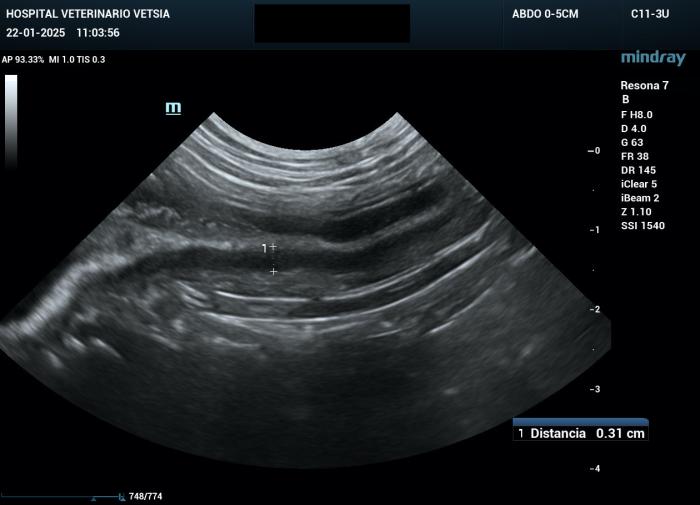

La ecografía abdominal evidenció un engrosamiento moderado de la mucosa y de la submucosa, y leve de la capa muscular del yeyuno y del íleon, generando un efecto masa transmural (Figura 2A-B).

Figura 2A-B. Imágenes ecográficas en las que se aprecia un engrosamiento de la mucosa y submucosa yeyunal, con alteración asimétrica de la capa muscular.

Figura 4A-B. Imágenes de ecografía abdominal sin signos de recidiva a los ocho meses tras el diagnóstico.